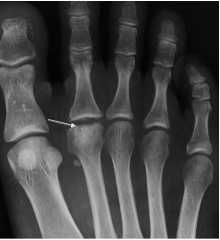

Freiberg’s disease with flattening and sclerosis of the 2nd metatarsal head (arrow)